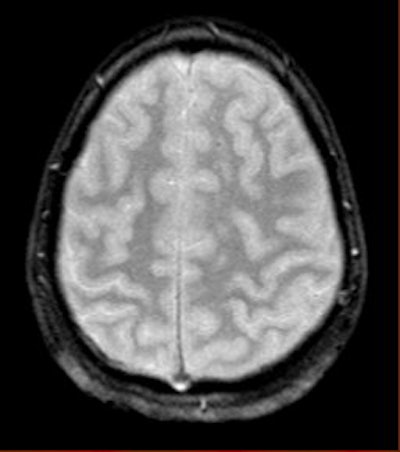

The reason for this reduction may be attributable to the increased iron content in these areas, Haacke explained. The iron can act like a paramagnetic contrast agent and shorten T1. SWI can use this phase difference to enhance the T1 contrast in an image (see below).

| An example of increased brain iron in gray matter changing local T1 as conceived by Robert Ogg, Ph.D., St. Jude Children's Research Hospital, Memphis, TN. The arrow shows the gray matter in the central sulcus. Note the poor contrast in the T1-weighted image and the excellent contrast in the phase image. Data collected on a 1.5-tesla system (Vision, Siemens Medical Solutions, Malvern, PA) with a TE = 40 msec by Larry Gates, Ph.D., Dalhousie University, Halifax, Nova Scotia. |